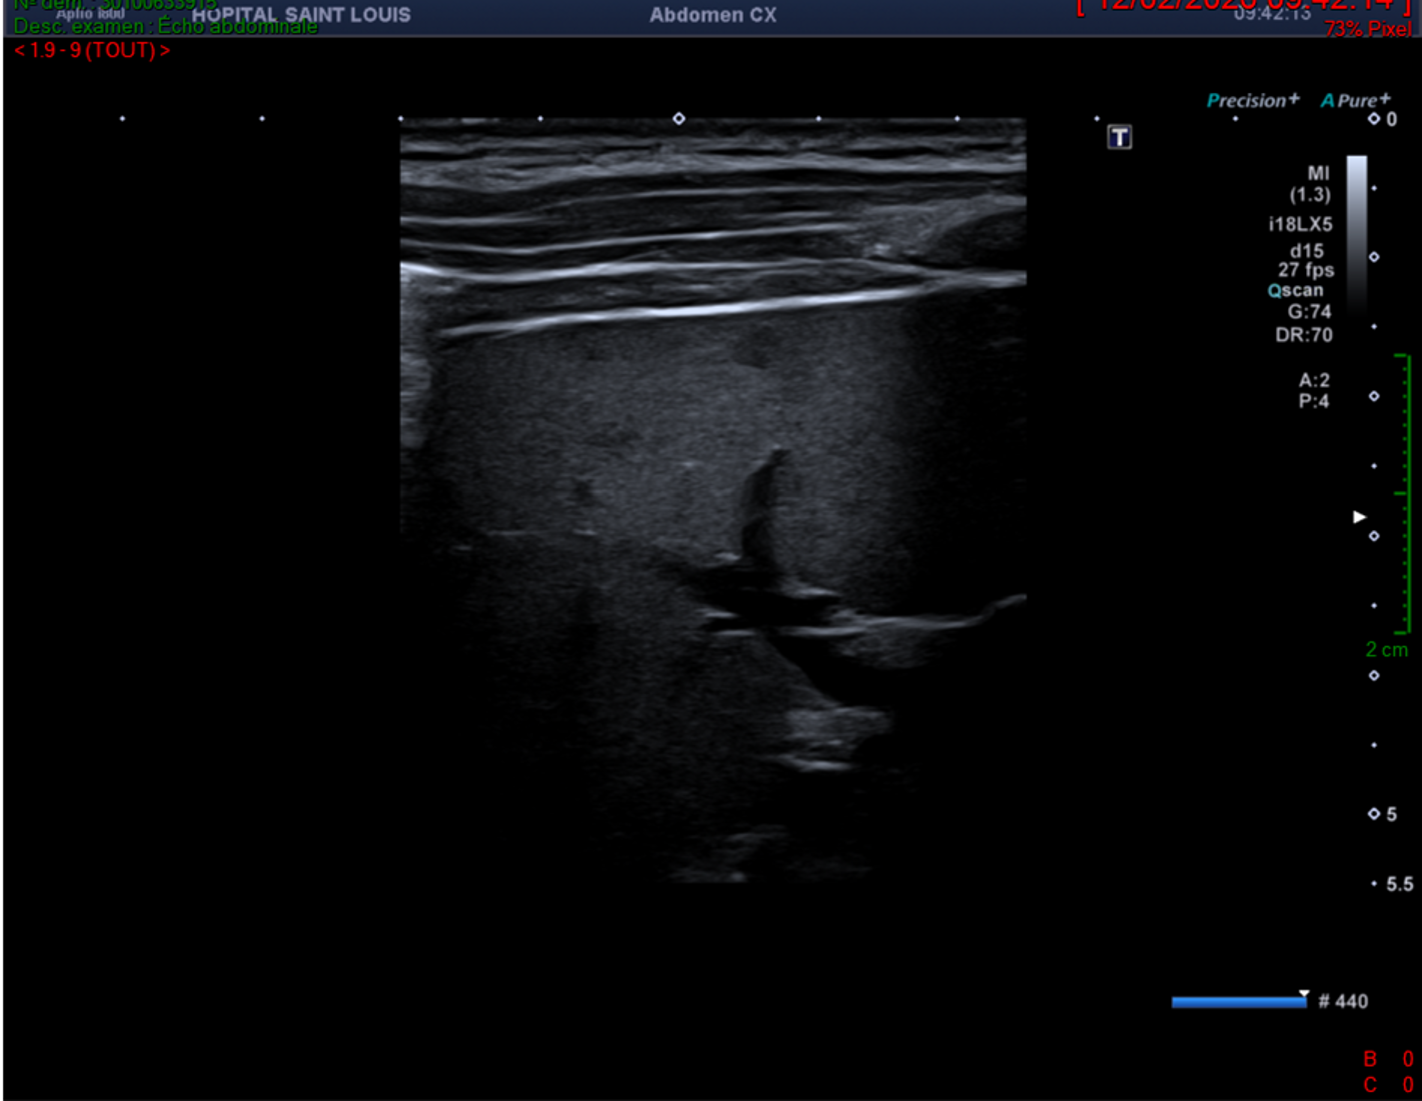

La rate semble homogène de taille normale avec une fréquence de 5.5MHz sur une sonde abdomninale.

Cependant, sur cette image la profondeur et la focale sont mal réglées. En effet la profondeur doit être adaptée à l’organe étudié, et sur cette image, il y a trop de profondeur. La focale aurait pu aussi être ajustée, en la remontant.

L’échographiste aurait pu arrêter son exploration là et conclure uniquement à une hépatomégalie homogène sans lésion focale ; mais il décide de la poursuivre en améliorant ses réglages et en utilisant des fréquences plus élevées. Il ne détecte rien de plus sur le parenchyme hépatique.

En revanche, voici le résumé des balayages qu’il effectue sur la rate en optimisant ses réglages (focale, fréquences et profondeur).